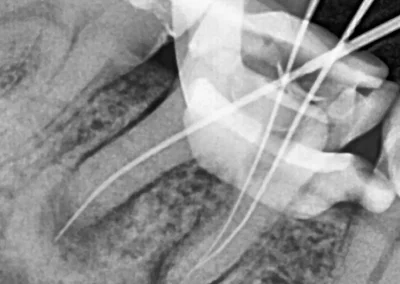

Temporomandibular Joint (TMJ) X-ray

If you feel pain near your jaw, face, or ear, a TMJ X-ray helps identify problems in the jaw joint or nearby muscles. It can also reveal small tooth cracks that aren’t visible during an exam.

Our digital system captures your jaw and bite in one image with minimal radiation, providing clear results quickly.